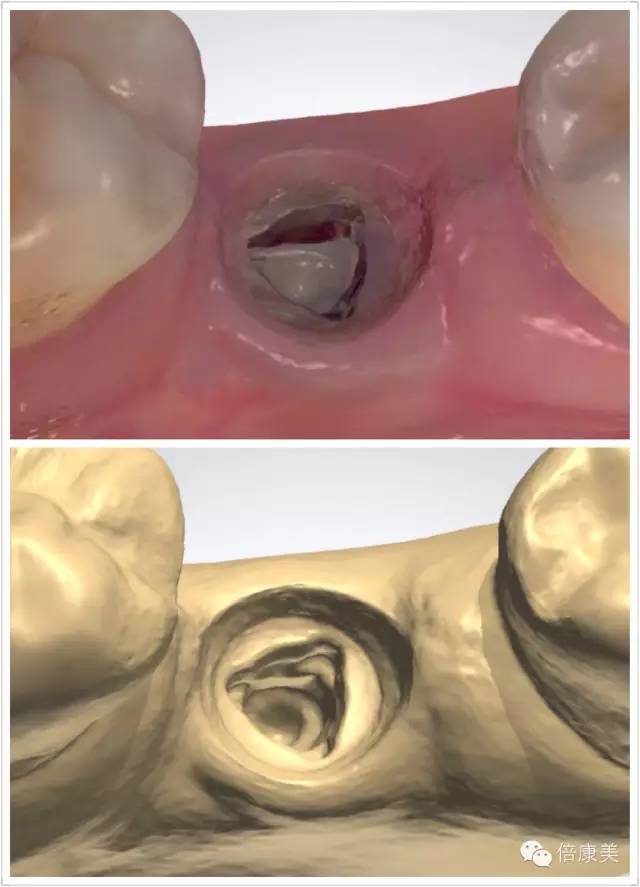

一次扫描即刻获取完整口内种植三维信息

超高清全真彩扫描还原口内真实情况

无接触式光学取像,避免了传统的硅橡胶取模对软组织的压迫